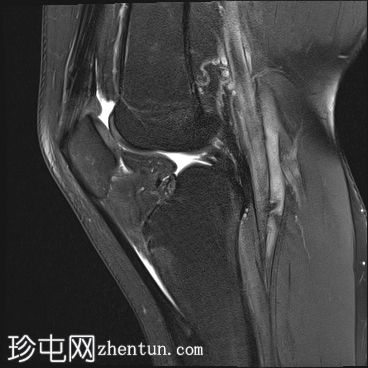

矢状面

T2

股骨内侧髁发育不全

胫骨髁间棘发育不全

腓骨头发育不全

前交叉韧带(ACL)和后交叉韧带(PCL)发育不全

髌腱延长,低位插入。

腘绳肌腱起源异常

外侧胫骨半月板韧带增厚;与外侧韧带(LCL)连接

术后可能出现股四头肌腱改变